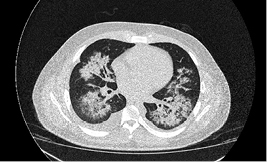

The patient was admitted with an initial diagnosis of pneumonia, being placed under an antibiotic therapy with levofloxacin 750 mg IV q24 hrs, along with oseltamivir, nebulized salbutamol, and budesonide. During his third day of stay he presented a sudden severe worsening of his clinical condition, with increased polypnea, tachycardia, dizziness and chest pain, which required the initiation of non-invasive mechanical ventilation, along with a transfer to the intensive care unit (ICU). The electrocardiogram (Figure 2), reported left ventricular hypertrophy as the most notable abnormality. A thorax CAT scan was performed (Figure 3), which showed signs of acute pulmonary edema. Suspecting a cardiopathy, an echocardiogram was performed (Figure 4), which showed a depressed ejection fraction of 19%, along with severe generalized hypokinesis.

Figure 3: High resolution thorax computed axial tomography, in which it can be seen the presence of multiple hyperdense zones in the pulmonary parenchyma, with an increase in liquid in the peribronchial spaces, indicative of acute pulmonary edema.